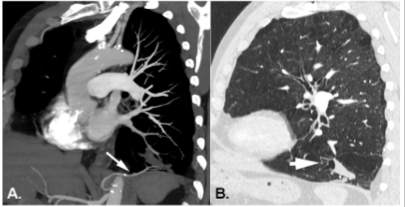

Leia o caso clínico a seguir.

Paciente do sexo masculino, de 61 anos, realiza angiotomografia do tórax para avaliação da aorta torácica. Como achado incidental, observam-se os seguintes achados no lobo inferior esquerdo (imagens A e B).

Os dados apresentados indicam que a alteração